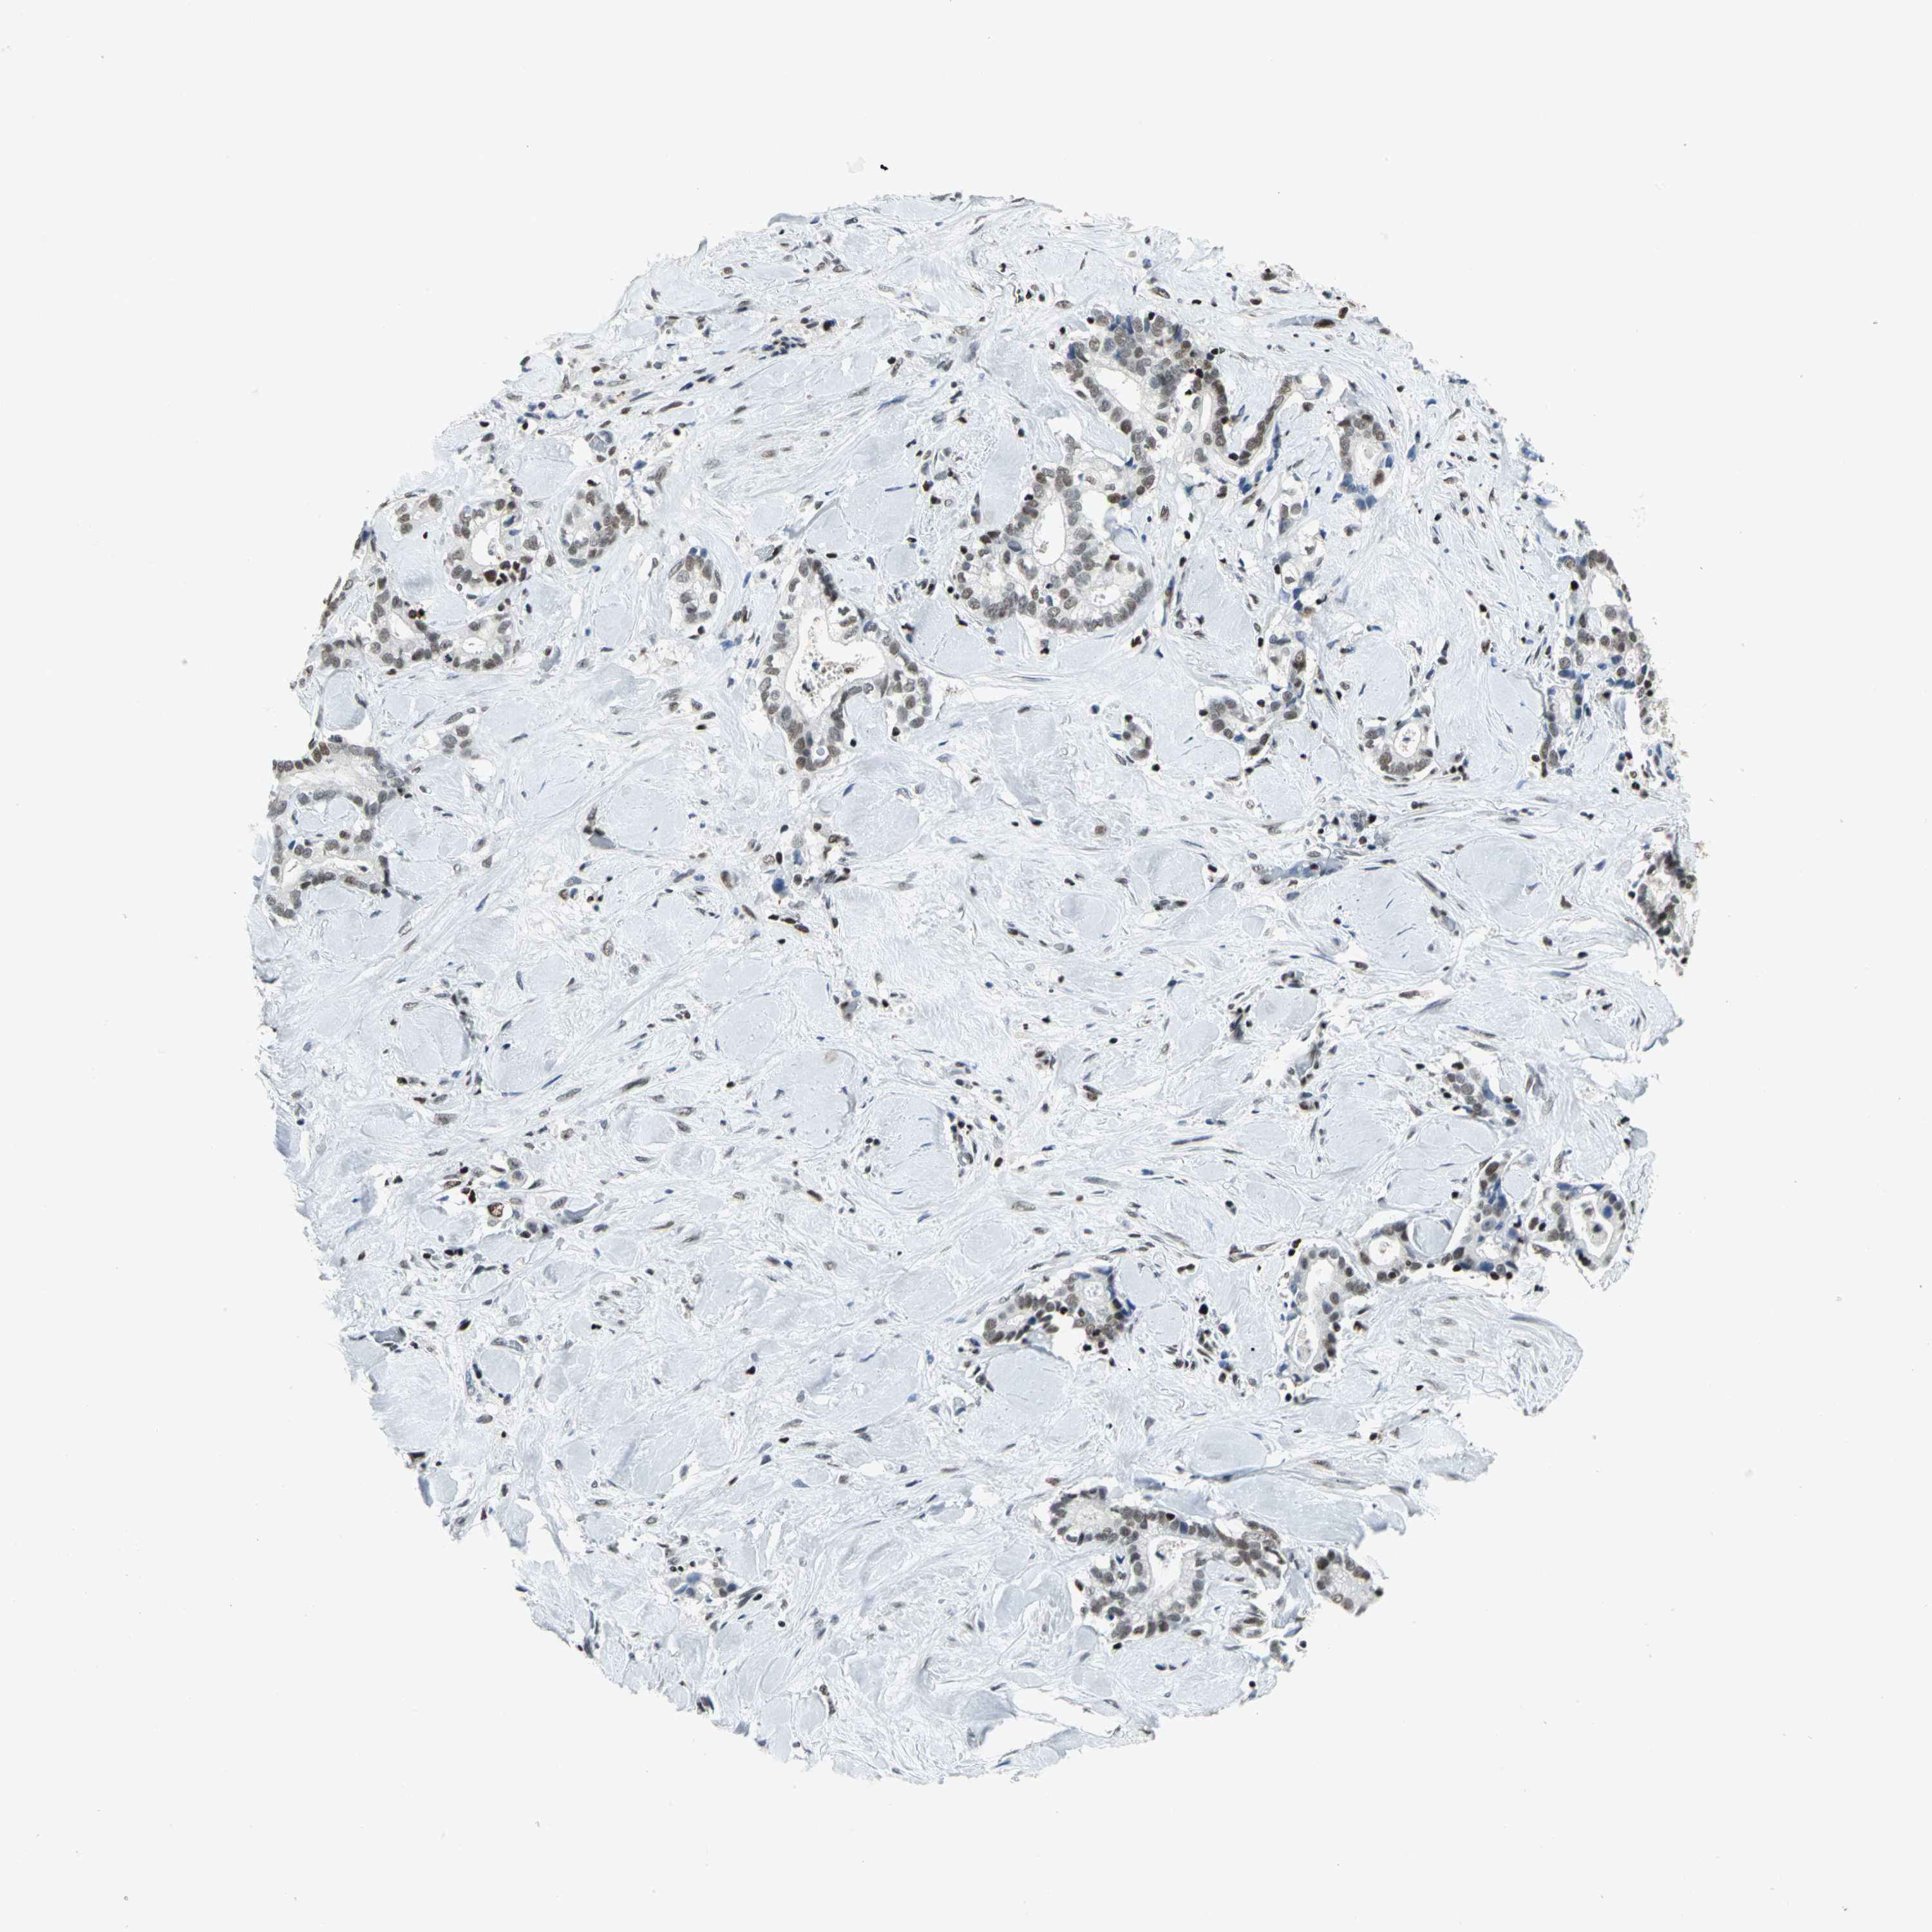

LIVER CANCER - Protein expressioni

A mouse-over function shows sample information and annotation data. Click on an image to view it in a full screen mode. Samples can be filtered based on level of antibody staining by selecting one or several of the following categories: high, medium, low and not detected. The assay and annotation is described here.

Note that samples used for immunohistochemistry by the Human Protein Atlas do not correspond to samples in the TCGA dataset.

Antibody stainingi

Antibody staining in the annotated cell types in the current human tissue is reported as not detected, low, medium, or high, based on conventional immunohistochemistry profiling in selected tissues. This score is based on the combination of the staining intensity and fraction of stained cells.

Each image is clickable and will lead to virtual microscopy that enables deeper exploration of all samples and also displays staining intensity scores, fraction scores and subcellular localization as well as patient and tissue information for each sample.

Antibody HPA004911

Staining

High

Medium

Low

Not detected

Intensity

Strong

Moderate

Weak

Negative

Quantity

>75%

75%-25%

<25%

None

Location

Nuclear

Cytoplasmic/membranous

Cytoplasmic/membranous,nuclear

Cholangiocarcinoma

Carcinoma, Hepatocellular, NOS